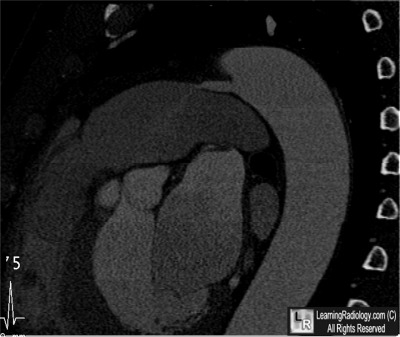

Sagittal CT Reconstruction through Heart

- Coarctation of the Aorta

5. Patent Ductus Arteriosus

Patent Ductus Arteriosus

- Persistent communication between the thoracic aorta and the pulmonary artery by the ductus arteriosus